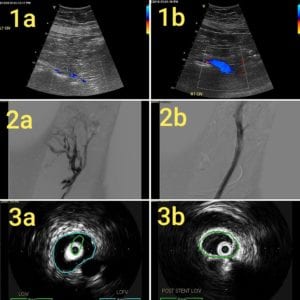

Authors: Tae An Choi ANP-BC, & Back Kim MD FACC. Heart Vein NYC, New York, New York Before (Right): 50 year-old male, a retail sales read more